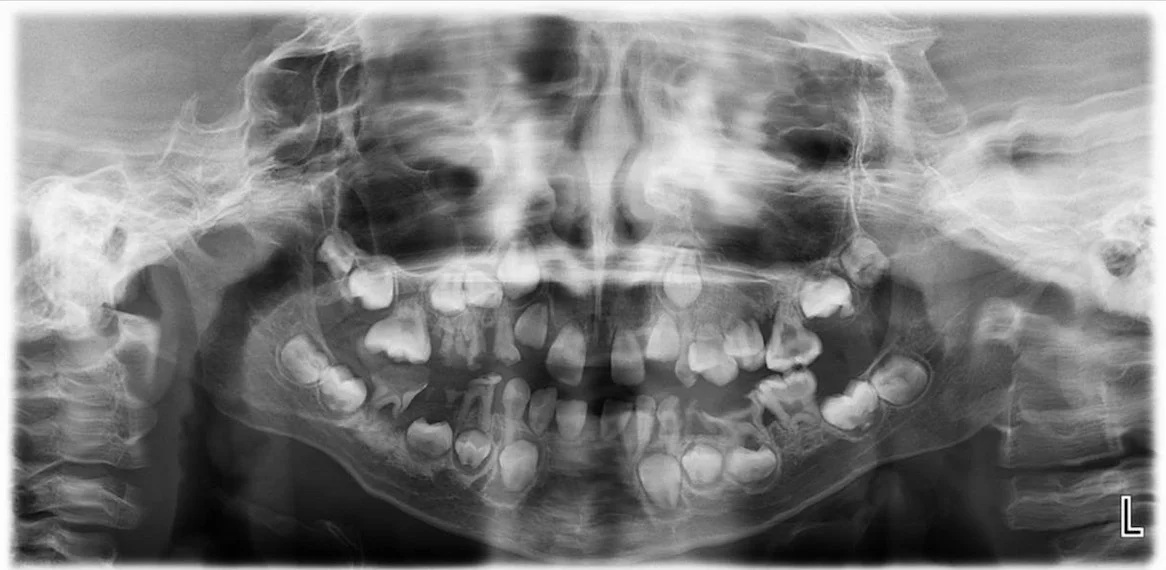

ناهنجاریهایی که روی دندانها تأثیر میگذارند نیز در سنین پایین در افراد مبتلا به سندرم سینگلتون-مرتن رخ میدهد. نوزادان مبتلا ممکن است دچار پوسیدگی (caries) شوند و به دنبال آن دندانهای شیری (deciduous) خود را زودتر از موعد از دست بدهند. برخی از دندانهای دائمی (erupt) ممکن است رشد نکنند یا ممکن است دیر رشد کنند و در صورتی که دندانهای دائمی رشد کنند معمولاً بدشکل هستند (dysplastic). در برخی بیماران، دندانهای دائمی نیز ممکن است زود از بین بروند.

تشخیص سندرم Singleton-Merten ممکن است در دوران شیرخوارگی بر اساس شناسایی علائم فیزیکی نوزاد (مانند ضعف و آتروفی عضلانی، ناهنجاریهای دندانی و تغییرات اسکلتی) قابل شناسایی باشند. تشخیص اولیه بیماری ممکن است با یک ارزیابی بالینی، شرح حال دقیق بیمار و انجام انواع آزمایشات تخصصی تایید شود. بررسی وجود رسوبات کلسیم در آئورت، در کنار سایر یافتههای شرح داده شده در بالا، مهر تاییدی بر تشخیص سندرم Singleton-Merten است.

آزمایشات اشعه ایکس (X ray) ممکن است برای تأیید وجود و میزان رسوبات کلسیم (calcifications) در آئورت و دریچههای قلبی استفاده شود. انسداد یا تنگی (stenosis) دریچههای قلب (به ویژه دریچههای آئورت و میترال) ممکن است با کاتتریزاسیون قلبی (cardiac catheterization) تایید شود.

آزمایشهای اشعه ایکس همچنین ممکن است منافذ توخالی بزرگ و غیر طبیعی قسمتهایی در استخوانها را که حاوی بافت چربی (حفرههای مغز استخوان) در استخوانهای دست و یا پا هستند (مانند metacarpals، carpals، phalanges)، نشان دهد.